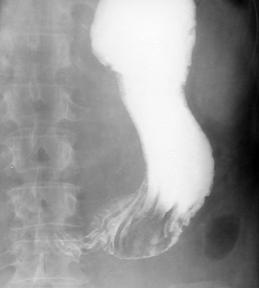

Nisele sunt plusuri de umplere care traduc existenta unei solutii de continuitate (ulceratiile), de suprafete si profunzimi variabile la nivelul peretelui tubului digestiv sau al unei mase tumorale, comunicand cu lumenul organului cavitar. Nisa maligna este o imagine aditionala care este "incastrata" in conturul lumenului, adica nu proemina. Suprafata este intotdeauna mai mare decat profunzimea, iar in incidenta ortograda este situata in interiorul unei lacune de dimensiuni variabile.

Regiunea nu isi modifica conturul la modificarea pozitiei, dar determina modificarea formei stomacului, datorita asocierii cu retractia portiunii afectate. De asemenea unei ulceratii i se descriu numarul, forma, dimensiunile, localizarea, contururile si structura. In cazul nostru caracterele ulceratiilor au fost reprezentate de multiplicitate si de faptul ca marginile lor nu au fost evidentiabile, avand corespondent radiologic conturul sters, imprecis delimitat sau neregulat.

Din totalul celor 38 de cazuri studiate, 14 au prezentat imagini lacunare realizand un procent de 36,84 % . Repartitia acestor cazuri in functie de tipurile histologice de limfom este prezentata in tabelul urmator.(fig. 43)

Fig. 45 - imagine aditionala cu aspect de nisa, localizata in interiorul unei lacune cu caractere maligne la nivelul antrului piloric